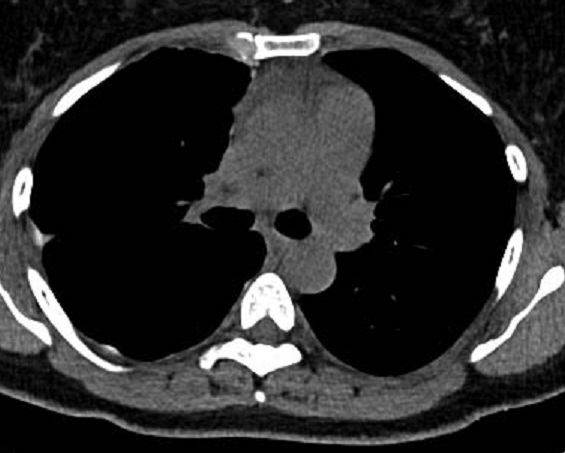

Même cas en coupe

sagitale . Aspect radiologique de epaissisement

pleural diffuse est de plaque opacite hyperdense ,

heterogene situe à inferieure , posterieure au sinus

coste-diaphragmatique posterieure droite . Image

radiologique TDM en coupe sagitale fenetre

mediastinale . |